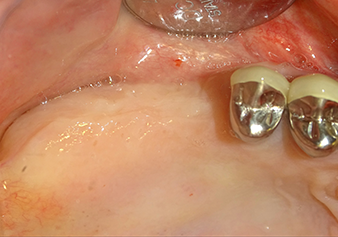

Implant bed preparation and augmentation

Following an intermediate check (Fig. 4) a further preparation step was performed (Fig. 5). Afterwards, the hydraulic Z35P instrument was used to lift the membrane to the desired position (Fig. 6 and 7). This was followed by further piezosurgical preparation of the implant bed, concluded with a rotary bur and shoulder milling cutter up to the implant diameter of 4.8 mm. Before the implant was inserted, the augmentation material (particle size approx. 0.8-1.6 mm) was introduced underneath the Schneiderian membrane (Fig. 8).